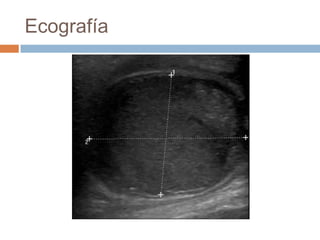

Ecografía

Urgencias 17/09

ECOGRAFIA y TC CERVICAL sin y con contraste ev.

Lesión de características quísticas que mide 35 x 40 x 48

mm de diámetros T, AP y L. Está localizada por detrás de

la glándula submaxilar izquierda, anterior y medial al

músculo ECM y desplaza a la carótida y yugular con las

que se identifica un plano de separación. Tras la

administración de contraste ev realza en periferia con las

paredes algo engrosadas observándose además realce en

ECM que está aumentado de tamaño. Pequeñas

adenopatías adyacentes de menos de 1 cm. No se ven

adenopatías aumentadas de tamaño de forma significativa.

Vía aérea permeable de calibre normal.

Conclusión.- Lesión compatible con QUISTE DEL

SEGUNDO ARCO BRANQUIAL con signos radiológicos

sugestivos de infección. Aconsejamos PAAF (citado 29/9) .